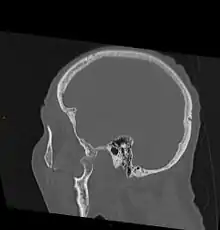

As with other joint dislocations, clinical history and examination are important for diagnosis. Commonly, plain and panoramic X-rays are used to determine the relative position of the mandibular condyle. If a complex or unusual injury is suspected, computed tomography is most reliable in diagnosing dislocation and possibly associated fractures or soft tissue injuries.

-

Bilateral anterior dislocation of the jaw -

Jaw dislocation following relocation -

CT image demonstrating jaw dislocation